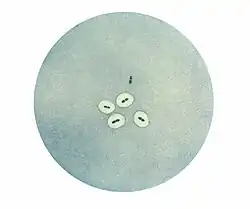

The quellung reaction, also called the Neufeld reaction, is a biochemical reaction in which antibodies bind to the bacterial capsule of Streptococcus pneumoniae, Klebsiella pneumoniae, Neisseria meningitidis, Bacillus anthracis, Haemophilus influenzae,[1] Escherichia coli, and Salmonella. The antibody reaction allows these species to be visualized under a microscope. If the reaction is positive, the capsule becomes opaque and appears to enlarge.

Quellung is the German word for "swelling" and describes the microscopic appearance of pneumococcal or other bacterial capsules after their polysaccharide antigen has combined with a specific antibody. The antibody usually comes from serum taken from an immunized laboratory animal. As a result of this combination, and precipitation of the large, complex molecule formed, the capsule appears to swell, because of increased surface tension, and its outlines become demarcated.